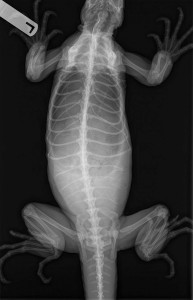

An egg bound iguana usually has a distended abdomen (technically the coelomic cavity). Depending on the number of eggs and their level of calcification these eggs can actually be felt when the abdomen is palpated. Radiography is used commonly to verify the diagnosis.

Can you visualize the numerous round and subtle swellings in the coelomic cavity (reptile equivalent of the abdomen) of this female iguana?

The numerous eggs in this female are a little easier to visualize

Our digital radiography machine gives us substantially better radiographs than the two above. Even though there are other factors like the amount of calcium on the eggs, and whether they are pre or post ovulatory, the difference between the old way and new way of taking radiographs is significant.